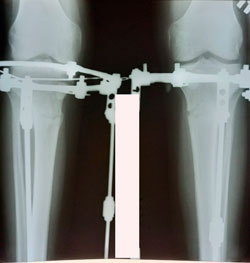

Исходник - 29 лет.

Дата операции - 29.09.2020

Мальчик